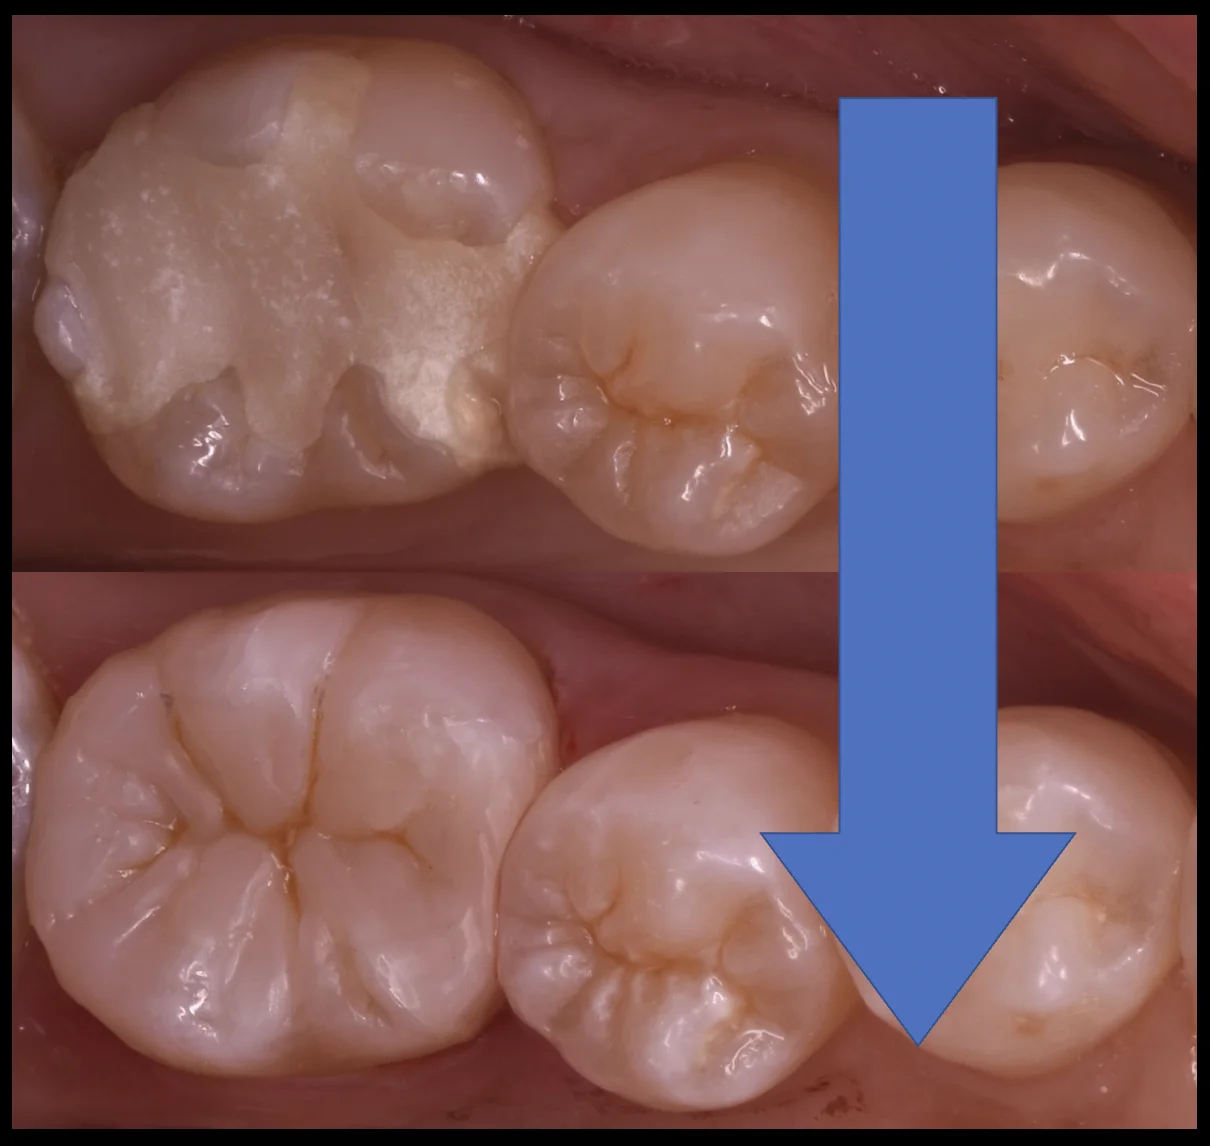

では術前の写真からです。

「詰め物が取れた」とのことで急患でいらっしゃったため、前回仮の蓋で封鎖している状態です。

仮のものですから当然色も合っていませんし、適合も良くありません。

仮の詰め物+虫歯を除去したのがこちらの写真になります。

内面が大きく括れており、非常に大きな虫歯であるのが分かります。

ですが、大きさに対して歯の表面部分は非常に多く残っていましたので、大イレクトボンディングの適応であると判断しました。

そして詰め終わり、噛み合わせの調整なども終了したのがこちらになります。

歯の溝の部分の色や、歯の溝の形は手前の歯に近づけるようにしたため、大きな違和感はないと思います。

詰めるのに時間がかかってしまったため、歯が強く乾燥してしまい、詰めた部分と歯の境目が分かりやすくなってしまっていますが・・・

これは1週間程度経てば勝手に水分が戻り馴染んでいきますので、特に問題はありません。

術前術後の比較はこんな感じです。